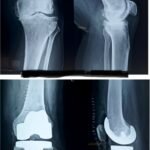

The use of robotics and computer navigation has revolutionized the way that knee replacement surgery is performed. The procedures can be performed with greater accuracy and allow more rapid recovery. Additionally, patients with previous injury or deformity of their knee who may have been once told surgery is not an option for them may be candidates for robotic-assisted procedures.

Yes, it can. The use of robotic or computer assistance adds an additional level of accuracy and precision to the procedure to ensure appropriate positioning of components and minimize soft tissue injury.

We have been able to make significant improvements in the components that we use during knee replacement surgery. Combining the newer materials with robotic assistance translates into better outcomes and increased longevity of implants.